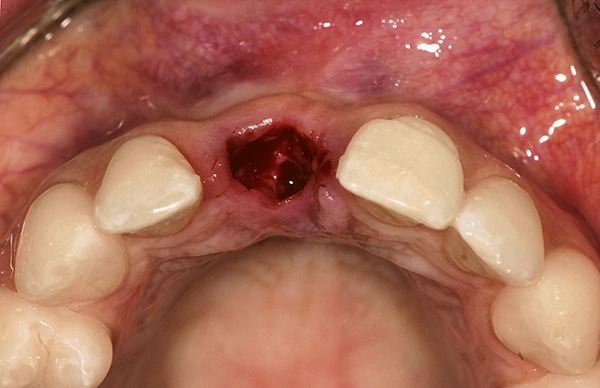

Nella foto in basso: nuovi fori dopo aver rimosso due denti contemporaneamente: